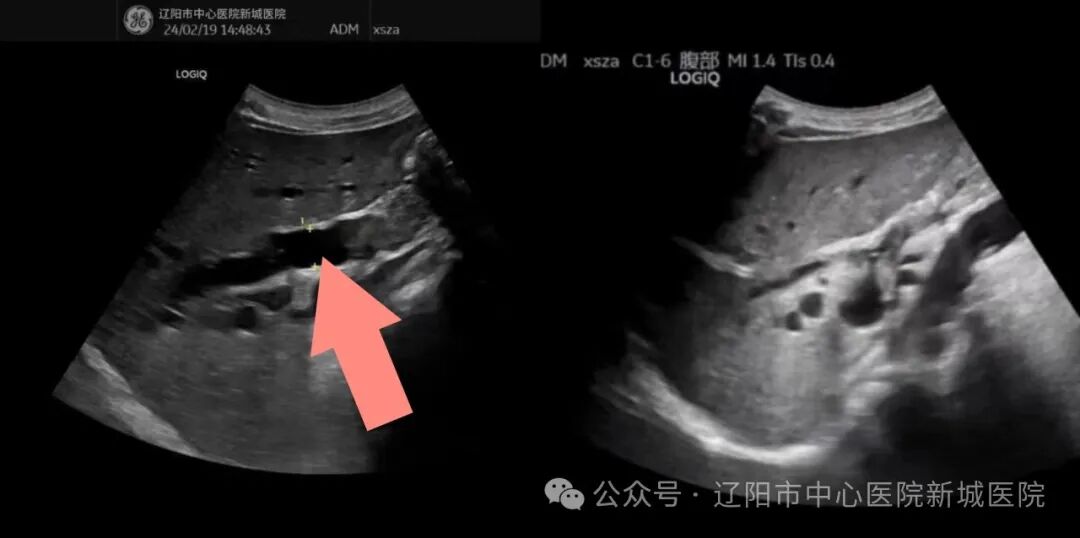

胆囊胀大

王大爷因上腹部疼痛伴全身黄染加重,皮肤瘙痒痛苦难忍受,曾在市内多家医院就诊,磁共振和CT的检查均提示:肝内胆管明显扩张,胆总管占位,胆囊胀大,胆汁潴留。

肝内胆管扩张

两位主任认真询问老人病史,结合磁共振和CT的检查结果,为老人进行细致的超声检查,进行精准诊断;并邀请了院内多位学科专家进行会诊,综合评估老人的病情,决定为老人进行超声引导下行经皮肝穿刺胆管引流术、经皮肝穿刺胆囊引流术,解除胆道双梗阻,提高生活质量。

张雅丽主任和刚玉恩主任共同为老人分步进行微创手术:首先采用超声引导下行经皮肝穿刺胆管引流术,穿刺针进入胆管,抽出白色透明胆汁100ml,超声显示左右肝内胆管扩张明显缓解,解决老人的肝内胆管扩张问题。然后采用经皮肝穿刺胆囊引流术,抽取胆汁120ml,超声显示胆囊明显缩小,解决了胆囊内胆汁潴留问题。术中老人没有不适感觉,术后安返病房,家属非常感谢两位主任给予的救治。老人于术后次日即康复出院。